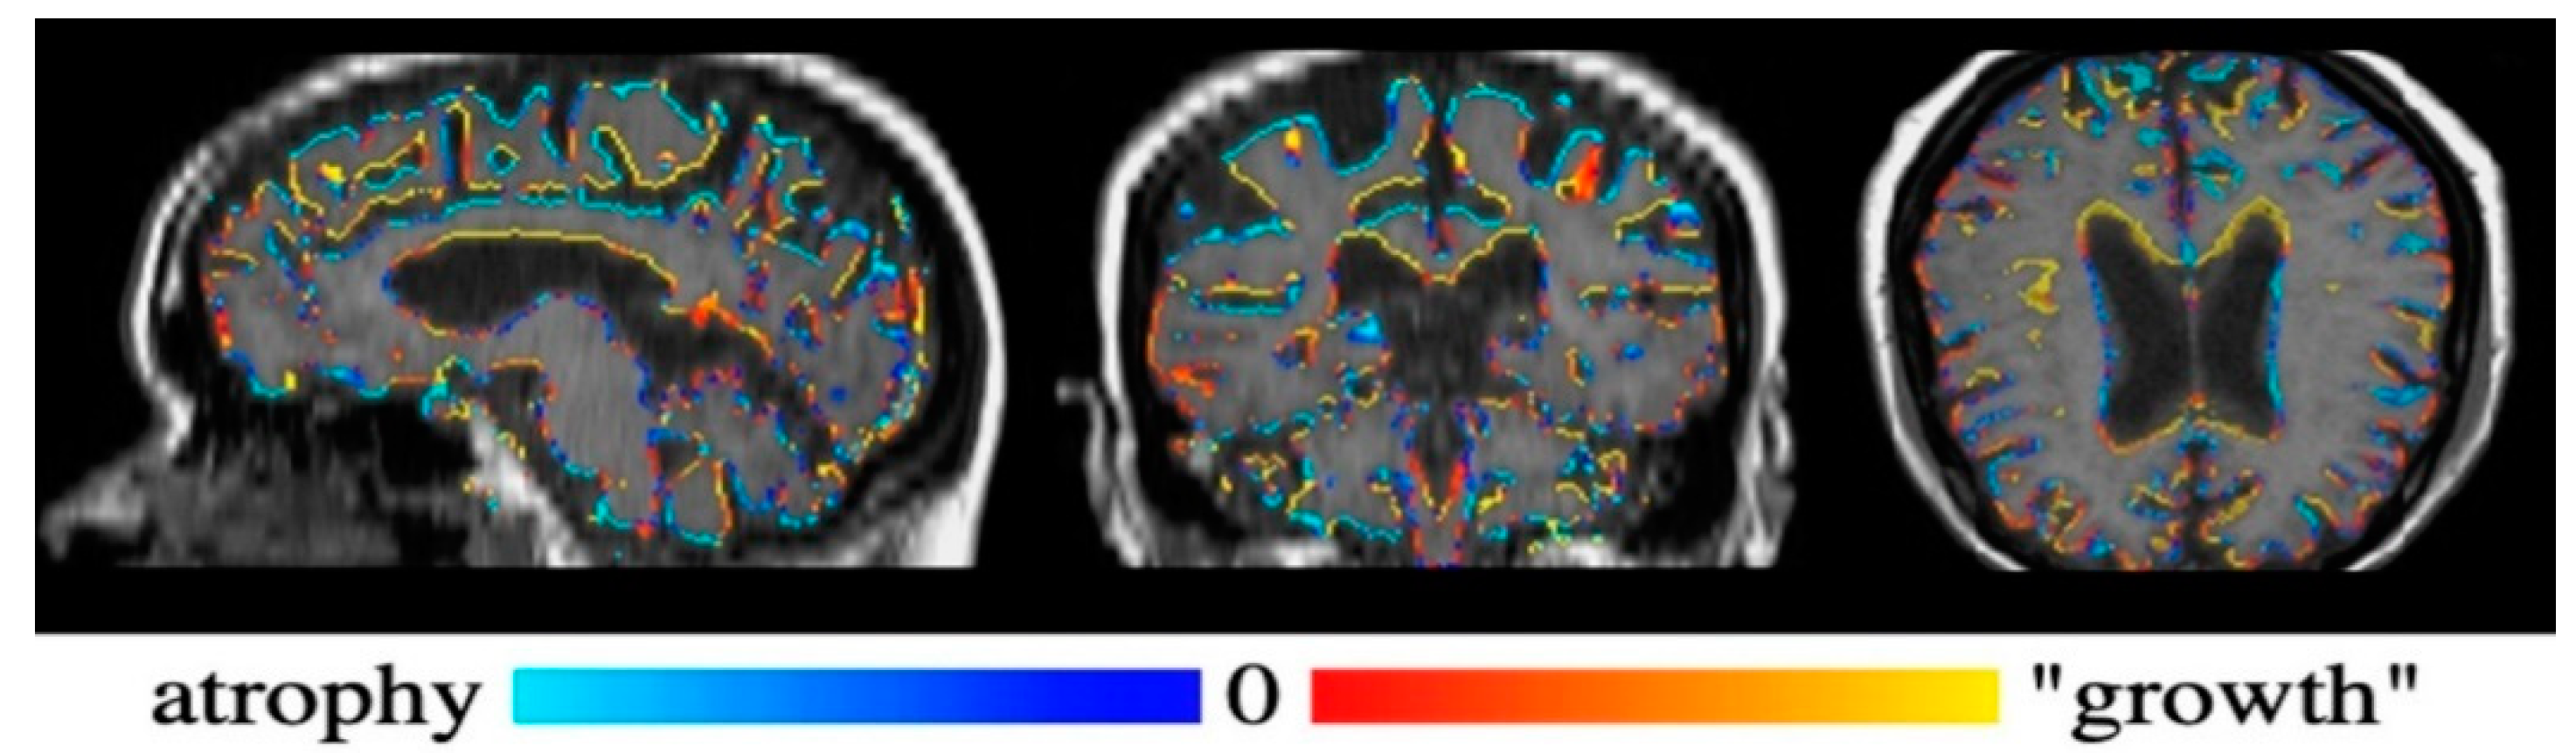

Figure 4 shows the Siena output color-coded image of the brain, while Figure 5 shows the brain parenchymal fraction in the axial image from August (Figure 5A) and September (Figure 5B), before and after DFPP procedure, respectively, with a TIV reduced by 2.14% in the latter, where subarachnoid spaces appeared to increase as expected.

Figure 4.

Siena output color-code imaged of the brain. Blue color indicates atrophy; red color indicates growth. Note the prevalence of blue in the grey matter and peripheral grey matter.

This reduction in the brain tissue volume resulted mainly from the shrinkage in grey matter and peripheral grey matter, measuring 511.2 mL and 402.9 mL respectively, according a % reduction of 1.16 and 1.14, respectively. The total cerebrospinal fluid (CSF) volume underwent a % net increase of 1.22, despite the ventricular space reduction by 1.11%. Finally, the white matter volume increased 1.14%. The patient underwent an intensive rehabilitation program with exercises focused on gait-reeducation and proprioceptive facilitation.

With regards to the paraclinical aspects of this case, the expected clinical improvement after DFPP cycles was associated with whole brain atrophy as detected in MRI post-analysis by Siena calculations. This phenomenon was consistent with a strong anti-inflammatory effect of DFPP on the nervous tissue, resulting in reduction of edema rather than tissue components, after the removal of humoral inflammatory elements from the blood. This property of so-called pseudoatrophy is common in other strongly anti-inflammatory DMTs, like Natalizumab, Interferon [22], and selective immune adsorption (SIA) [12]. Detectable disease-related brain atrophy requires at least 3 months to take place, as it depends on slowly developing neurodegenerative mechanisms [23]. The detection of pseudoatrophy of the brain, even in a case of relapse sustained by cervical lesions, proves the spread of inflammation in MS also occurs at very distant sites from the acute demyelinating lesion, including to virtually the entire CNS.